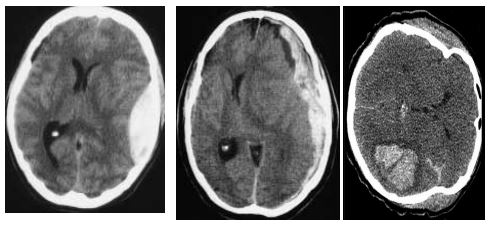

Qui di seguito sono riportate schematicamente le sedi, dove maggiormente si localizzano gli ematomi e alcune immagine di TAC del cranio che mostrano alcune lesioni cerebrali.

Ematoma extra durale, ematoma sub-durale emorragia intracerebrale

Nel trauma cranico severo di secondo grado il punteggio GCS è inferiore a 9 è caratterizzata ad alterazione grave e persistente dello stato di coscienza e può essere associato a emorragie cerebrali, fratture delle ossa craniche e del massiccio facciale. Tutti i soggetti con trauma cranico grave necessitano di ricovero e di TAC cranio in urgenza insieme alla radiografia del colonna cervicale e consulto da parte del neurochirurgo in urgenza.

La TAC cranio rappresenta l’esame più indicato per determinare la presenza e l’estensione di un eventuale danno cerebrale in corso di trauma cranico. La metodica è utile per evidenziare e quantificare il danno cerebrale e la presenza di eventuali fratture del cranio, è utilizzata anche per lo studio della colonna cervicale.